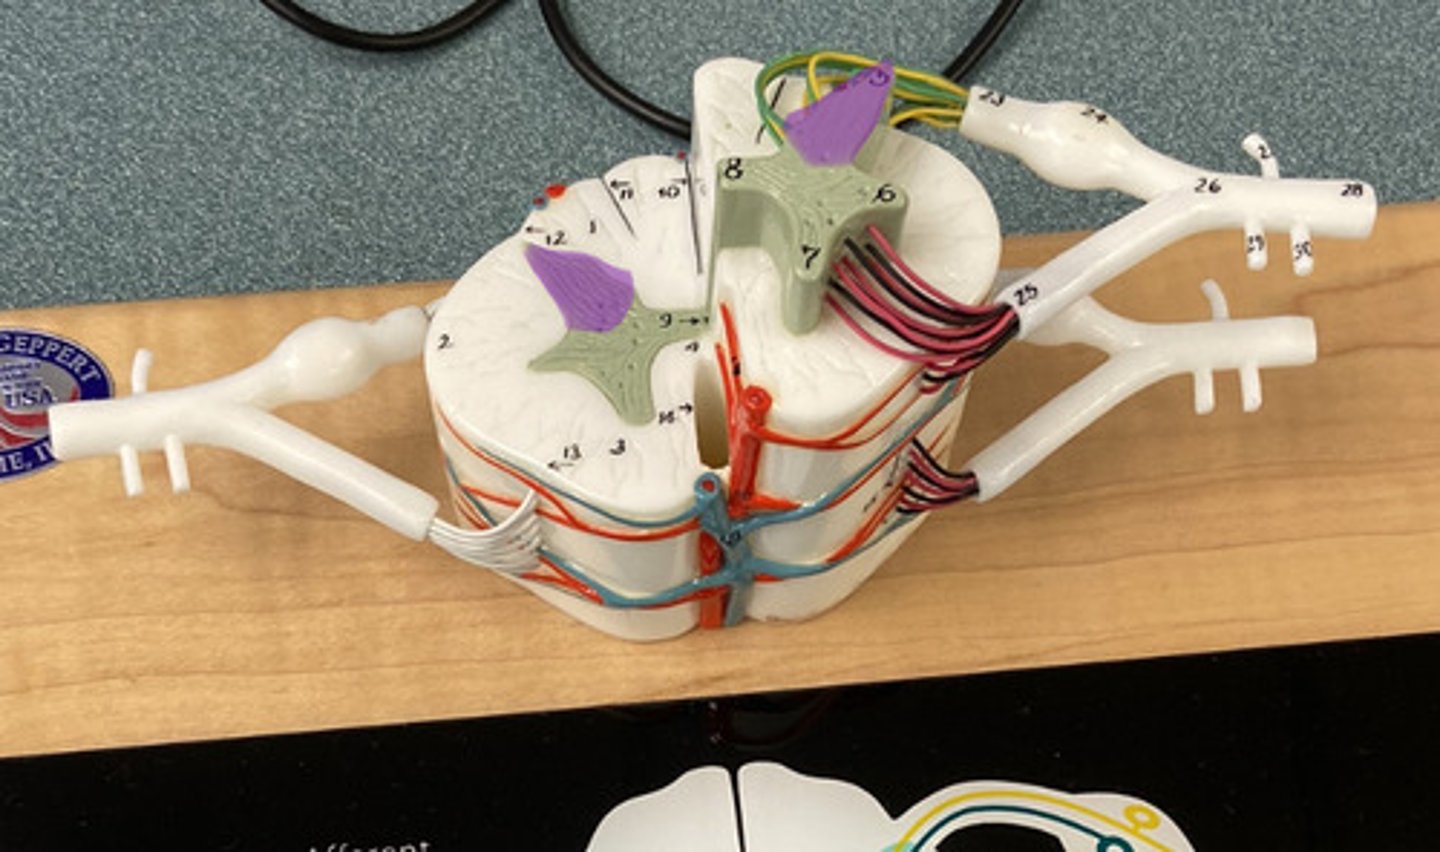

White Columns/ Matter

Gray Matter

Dorsal Horn

Lateral Horn

Dorsal (posterior) Median Sulcus

Ventral (anterior) Median Fissure

Central Canal

Ventral Root

Dorsal Root

Dorsal Root Ganglion